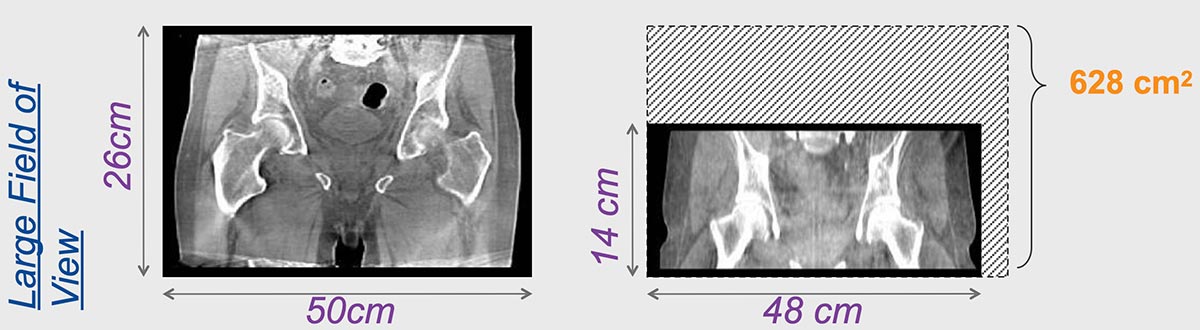

Elekta Synergy® provides unparalleled clinical assurance to more aggressively treat tumors while keeping damage to surrounding healthy tissues to a minimum. Elekta Synergy®‘s precision accuracy reduces or eliminates the use of markers because clinicians can view soft tissue using Elekta Synergy®‘s VolumeViewTM. The low-dose imaging proficiency helps minimize the side effects of radiation therapy by decreasing the margins previously set to account for the unpredictability of target location, movement, and dimensions.